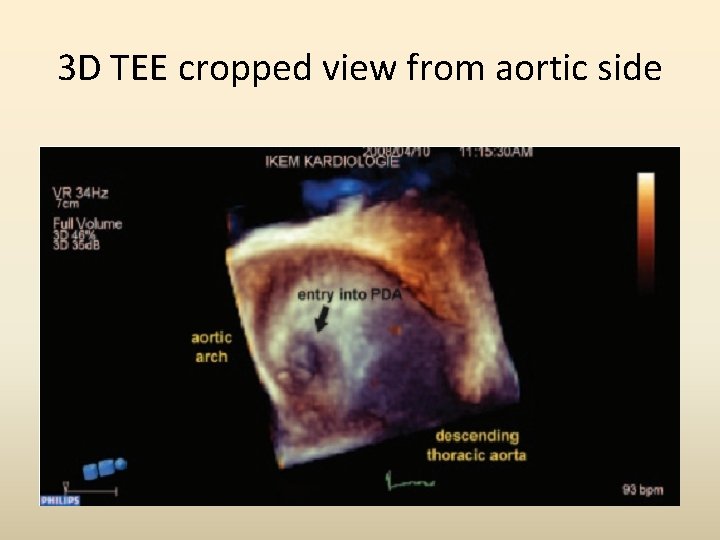

3 D TEE cropped view from aortic side